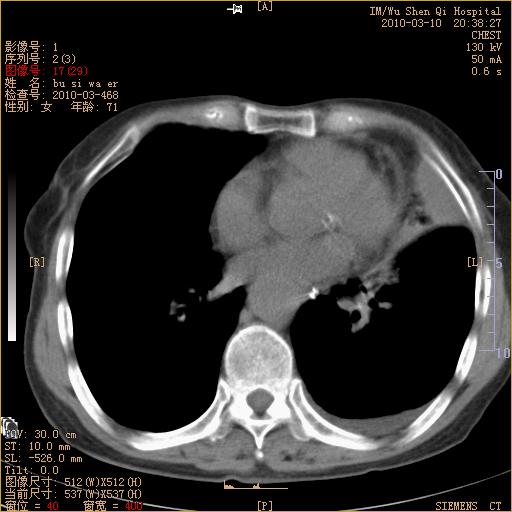

以下是引用随光逐影在2010-3-11 0:41:00的发言:[br]1)考虑左肺及右肺上叶继发性肺结核并左肺炎症感染。2)左侧支气管内膜结核可能;建议必要时行纤支镜检查。3)肺气肿。4)心包膜增厚(或少量心包积液)。5)左侧胸腔积液。